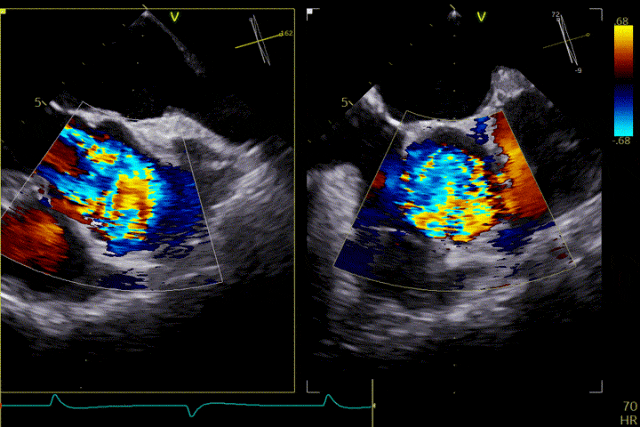

在超聲引導下,手術團隊高效精準地完成了瓣膜的定位、釋放與功能評估。手術過程順利,夾持件入竇與定位一氣呵成,三枚夾持件的釋放與錨定位置與術前評估完全一致,器械操作時間約5分鐘。術中超聲評估顯示無瓣周漏,血流動力學表現穩定,手術過程順利。

瓣膜釋放

患者主動脈瓣重度反流糾正,術后無反流、無瓣周漏。術后心臟彩超顯示人工生物瓣啟閉良好,平均跨瓣壓差2mmHg,流速正常。患者恢復情況良好,心功能較術前有了明顯改善。